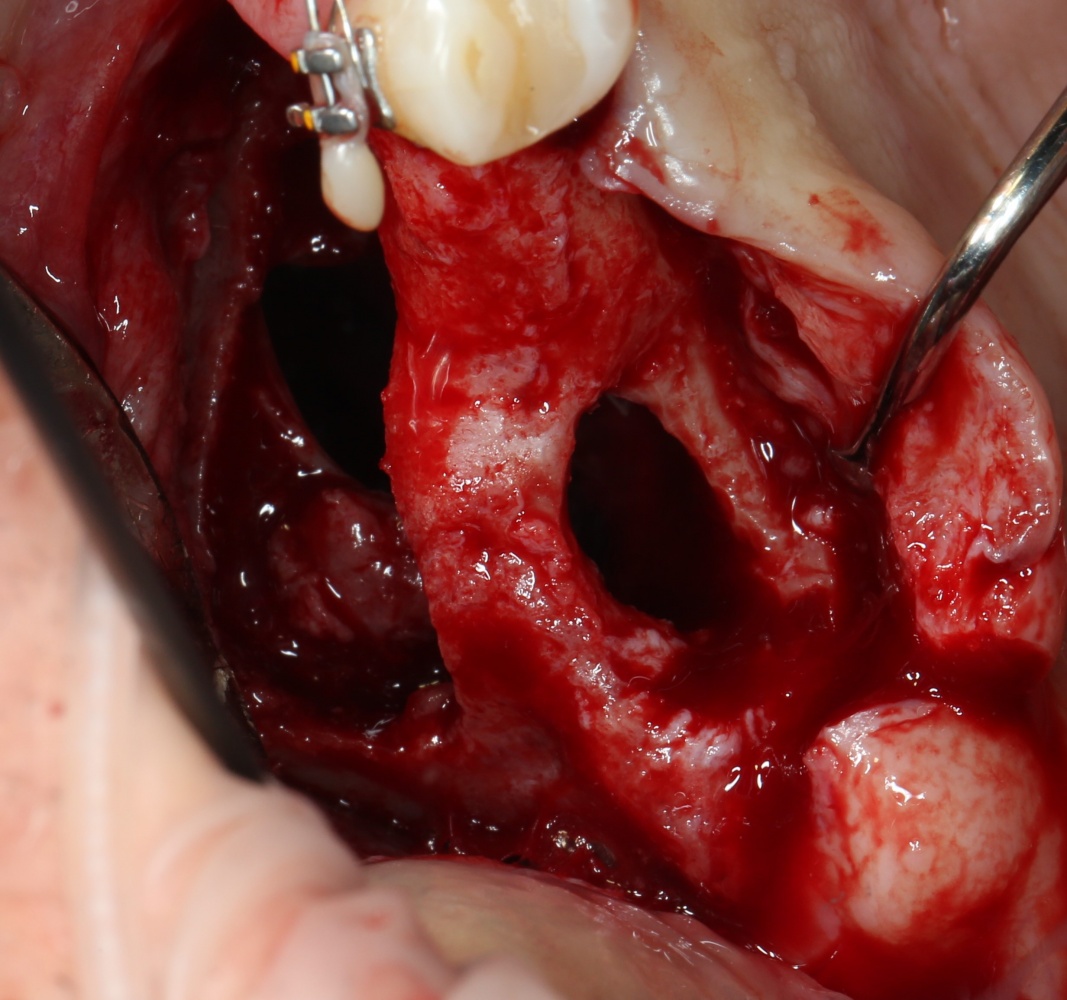

Итак, Зинаида на приеме.

Вот клиническая картина через 4 месяца после ранее проведенной имплантации с остеопластикой:

Как видишь, коллеги из недалекой дружественной страны не осилили снятие швов. Мне это не нравится, хотя и объясняет, почему люди готовы ехать за тыщи километров ради 20-минутной операции удаления зуба мудрости.

Ну хорошо. Швы сняли. Делаем разрез. Обрати внимание, что после всех проведенных операций у нас остается очень небольшой по ширине слой жевательной слизистой оболочки: